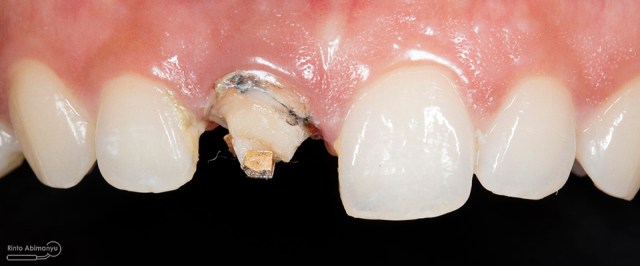

Kasus hari ini tentang gigi-gigi anterior yang fraktur karena kecelakaan lalu lintas. Pasien datang menceritakan kejadian yang dialaminya dan meminta saran bagaimana sebaiknya tindakan yang dilakukan pada giginya…

Kalimat yang saya ingat betul dari pasien adalah “Dok, tolong kembalikan senyum saya lagi.” ……..kalimat sederhana tapi membuat saya memikul tanggung jawab yang berat…

Begini kondisi klinis saat datang…

Foto klinis gigi-gigi anterior yang mengalami fraktur

Foto klinis setelah pemasangan crown

Alhamdulillah pasien nya senang sekali…. dia puas dan saya pun senang karena dapat memenuhi keinginan pasien…..

Nah ini resume foto before dan after perawatannya…